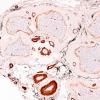

PERIPHERAL NEUROPATHY

1 NORMAL NERVE ANATOMY

2 Normal IHC